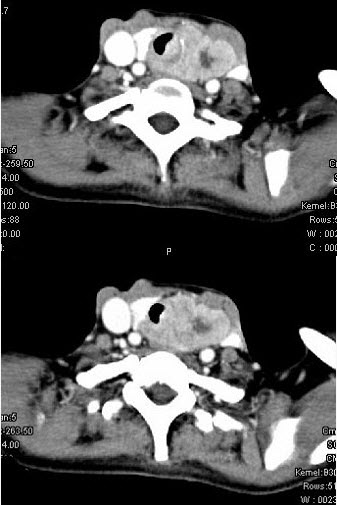

女,50岁,左下颈部扪及一质硬、表面高低不平的包块,肿块逐渐增大,现感吞咽困难,CT如图所示,最可能诊断为()。

A、甲状腺癌

B、食管癌

C、喉癌

D、甲状腺原发淋巴瘤

E、颈部神经鞘瘤

A